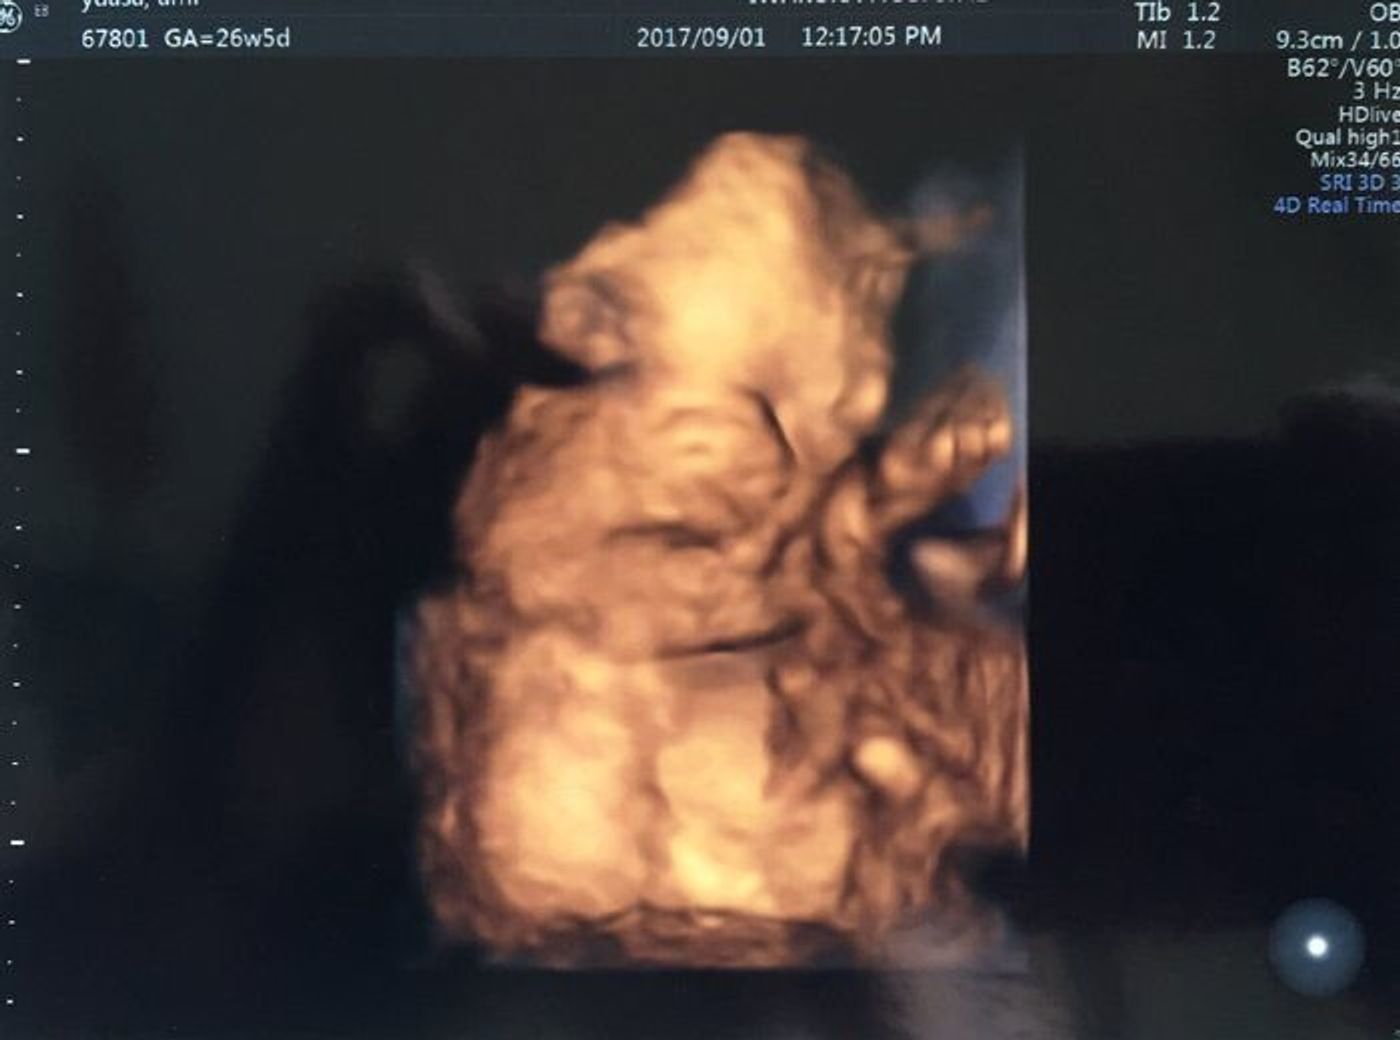

赤ちゃんの性別判断お願いします 現在第三子妊娠中で26週目にな Yahoo 知恵袋